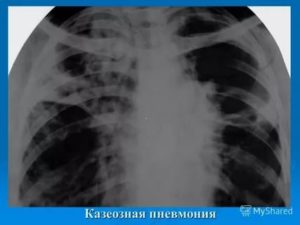

Казеозная пневмония фото

Казеозная пневмония развивается у лиц со значительно ослабленным иммунитетом. Клинические симптомы заболевания ярко выражены и соответствуют клинике острого воспаления легочной ткани.

На рентгенограмме видны интенсивные тени казеозного некроза и множественные полости распада. Процесс быстро распространяется по бронхам, поражая обширные участки легочной ткани. МБТ выделяются во внешнюю среду в огромном количестве.

Рис. 3. На фото казеозная пневмония. На рентгенограмме видны интенсивные тени казеозного некроза и множественные полости распада. Процесс распространился по бронхам и поразил обширные участки легочной ткани.